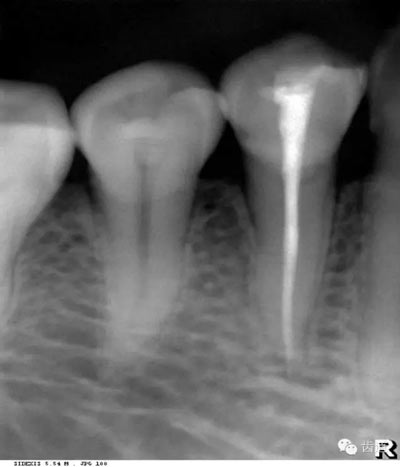

髓腔可分為冠部的髓室和根部的根管。牙髓內(nèi)含牙髓軟組織,X線片上顯示為密度低的影像。年輕人的牙、牙根未完全形成時,根尖孔粗大,牙髓腔大。隨著年齡的增長,牙本質(zhì)逐漸增多,髓腔愈狹窄,根尖逐漸變細(xì)。